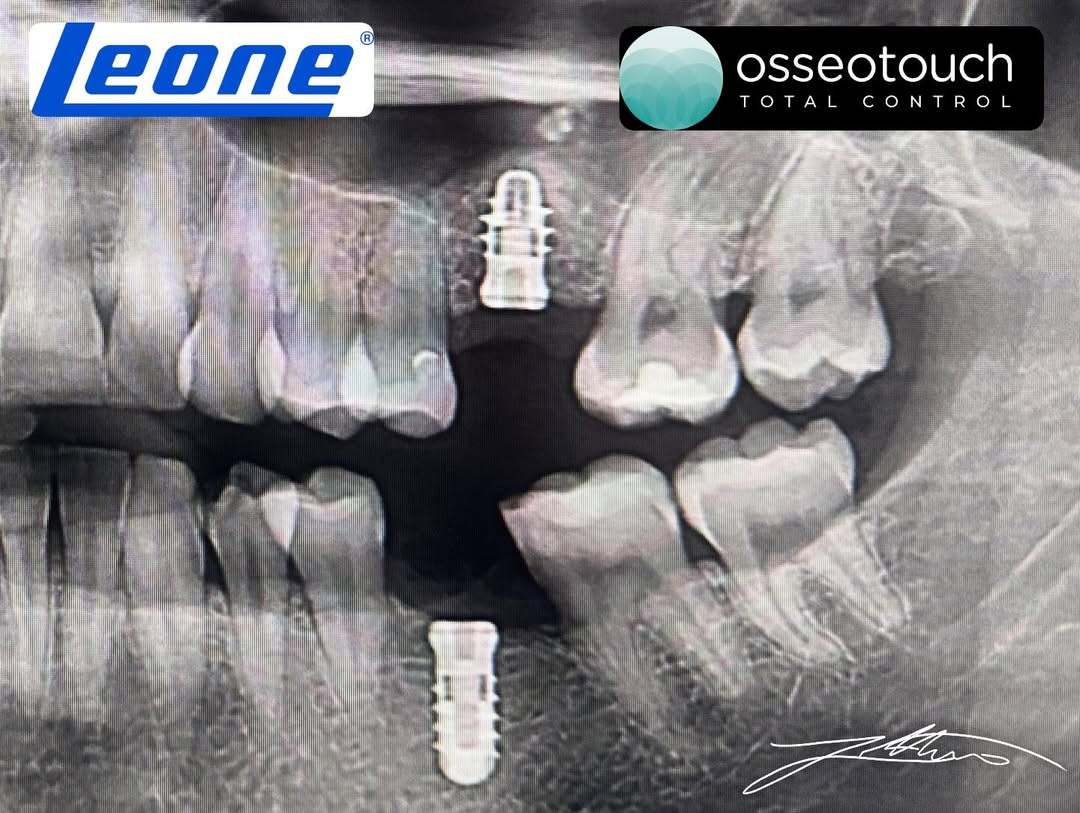

Pas arritjes së lartësisë së planifikuar, u vendos një implant dentar me dimensione 3.5 × 8 mm, duke përfituar nga stabiliteti i krijuar përmes ngritjes krestale të sinusit. Zona kirurgjikale u mbyll më pas me suturë, duke përfunduar procedurën kirurgjikale në mënyrë të kontrolluar dhe të sigurt.

Ekzaminimi CBCT pas operacionit konfirmoi:

• Pozicionimin korrekt të implantit dentar

• Ngritjen e suksesshme të sinusit maksilar

• Integritetin e membranës së Schneider-it

• Karakterin atraumatik të procedurës së realizuar

Këto rezultate u arritën falë saktësisë së impulseve magneto-dinamike të Magnetic Mallet, të cilat lejojnë një transferim energjie shumë të shpejtë dhe të kontrolluar, pa krijuar trauma të panevojshme.